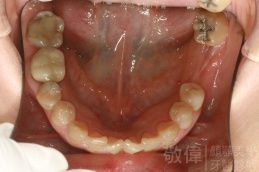

治療前-下顎全口   治療後-下顎全口